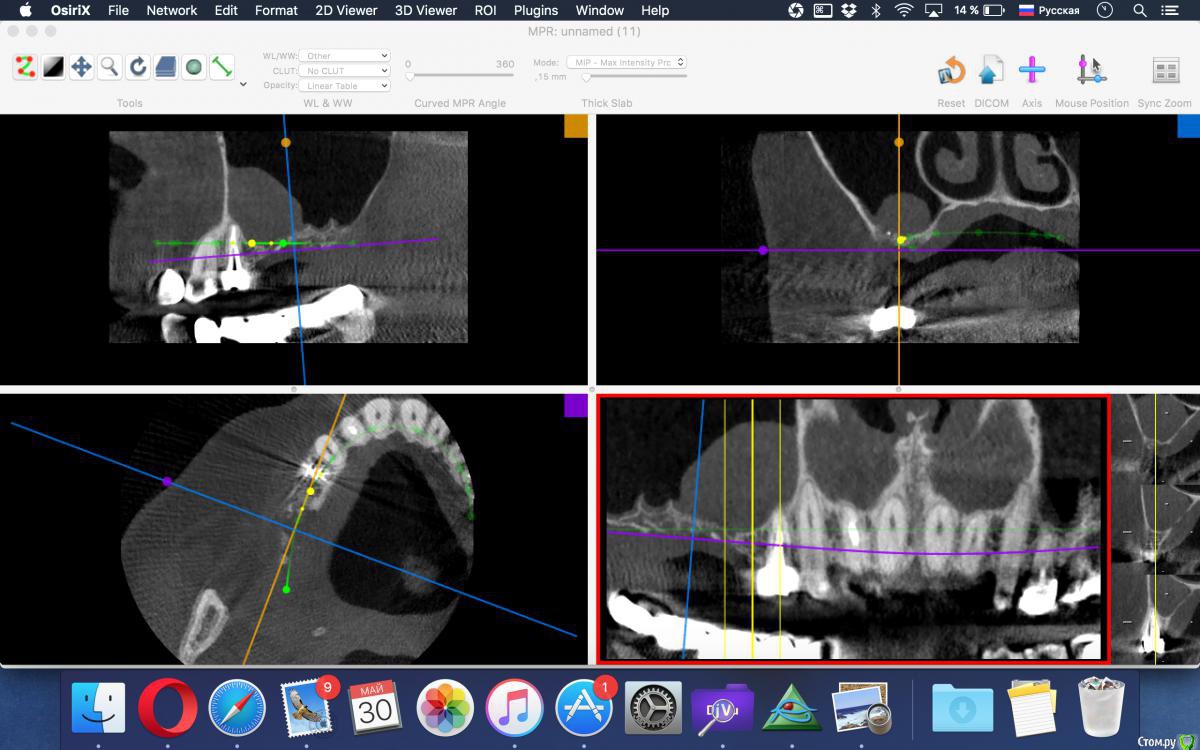

ivanov6988 Опубликовано 30 мая, 2017 Поделиться Опубликовано 30 мая, 2017 Добрый день. Дабы не плодить темы по тактике всяких утолщений продолжу здесь.Клкт через 6нед после удаления 1.7 Планирем синуслифт+импл в поз 1.7 1.5, Как бы вы поступили? Пойти крестально на синус в обл 15+ латерально окно для аспирации содержимого илисделать два окна выше/ниже иливообще отслаивать как при обычном ибо это не киста а полип Ссылка на комментарий

kamranchick Опубликовано 30 мая, 2017 Поделиться Опубликовано 30 мая, 2017 Добрый день. Дабы не плодить темы по тактике всяких утолщений продолжу здесь.Клкт через 6нед после удаления 1.7 Планирем синуслифт+импл в поз 1.7 1.5, Как бы вы поступили? Пойти крестально на синус в обл 15+ латерально окно для аспирации содержимого илисделать два окна выше/ниже иливообще отслаивать как при обычном ибо это не киста а полип все зависит от ваших манульных навыков, можно и аспирировать жидкость можно не аспирировать, я бы не аспирировал и пошел бы двух этапно, сначала синус, через 6 месяцев повторное кт и оценил бы ситуацию для последующей имплантации. и посмотрите может это все от 4 зуба, на мой взгляд целесообразно удалить зуб 4 и установить имплантат 4 - 6 так как в области 7 го зуба неровности, при выполнения синус лифтинга будут определенные риски, плюс на нижней челюсти длинный мост стоит, скорее всего не особо надежный Ссылка на комментарий

Bier Опубликовано 30 мая, 2017 Поделиться Опубликовано 30 мая, 2017 Добрый день. Дабы не плодить темы по тактике всяких утолщений продолжу здесь.Клкт через 6нед после удаления 1.7 Планирем синуслифт+импл в поз 1.7 1.5, Как бы вы поступили? Пойти крестально на синус в обл 15+ латерально окно для аспирации содержимого илисделать два окна выше/ниже иливообще отслаивать как при обычном ибо это не киста а полип Делается 2 доступа, если делать классически, через латеральное окно, то нужно вначале сделать доступ очень высоко, у самой вершины образования (небольшой, под размер слюноотсоса). Сначала аспирировать содержимое, потом вытянуть образование отсосом и пинцетом. После этого спокойно делать синуслифтинг с доступом несколько ниже. Либо крестально, но смысла уже нет крестальный доступ делать, раз уж лоскут все равно откинете. 1 Ссылка на комментарий

ivanov6988 Опубликовано 19 ноября, 2017 Поделиться Опубликовано 19 ноября, 2017 Делается 2 доступа, если делать классически, через латеральное окно, то нужно вначале сделать доступ очень высоко, у самой вершины образования (небольшой, под размер слюноотсоса). Сначала аспирировать содержимое, потом вытянуть образование отсосом и пинцетом. После этого спокойно делать синуслифтинг с доступом несколько ниже. Либо крестально, но смысла уже нет крестальный доступ делать, раз уж лоскут все равно откинете.Спасибо. КЛКТ контроль спустя 5мес. Раскрываем Ссылка на комментарий